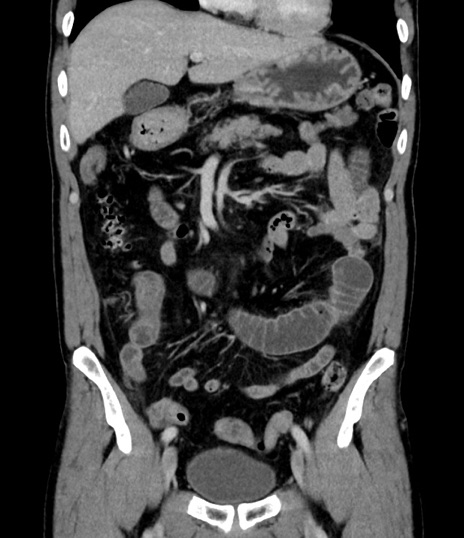

症例8(冠状断像)

【症例】 60歳代男性

【主訴】 黒色吐物

【現病歴】 4日前から嘔気自覚、2日前の朝食後にも嘔気あり、自分で手で嘔吐反射起こし嘔吐したところ血が混ざっていたため受診。

【既往歴】 5年前汎発性腹膜炎を伴う急性虫垂炎で手術、高血圧、前立腺肥大症、高脂血症

【身体所見】 腹部正中に手術癩痕あり 腹部平坦・軟圧痛なし膨満感あり

【データ】WBC 8400、CRP 4.54